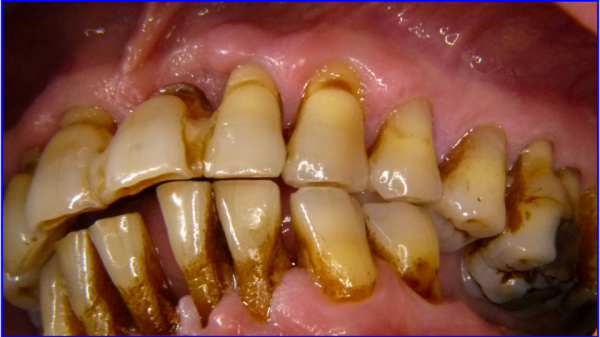

Die klinisch obligaten Symptome der NUG sind starke Schmerzen, Nekrosen und Ulzerationen der Interdentalpapillen und spontane gingivale Blutungen (Abb 3).

Abb 3: Nekrotisierende Parodontalerkrankung mit nekrösem Zerfall der Interdentalpapillen

Als weitere Symptome kommen oft Fieber, ein deutlich herabgesetzter Allgemeinzustand, Foetor ex ore und eine Lymphadenitis hinzu. Ein Soldat mit einer NUG ist nicht einsatzfähig. Er bedarf stets einer zahnärztlichen Notfalltherapie, unbehandelt kann es zu massiven irreversiblen Gewebsdefekten kommen.